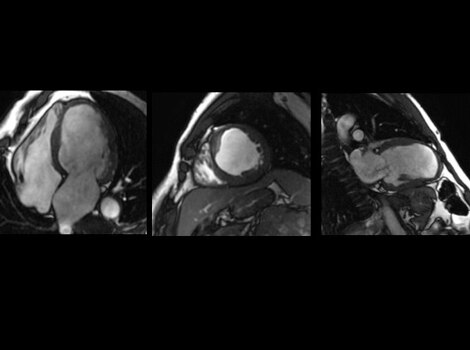

SIGNA Works CV Imaging & Analysis Tools

A free breathing, cardiac MR to assess cardiac morphology,function, flow, tissue viability and coronary anatomy without ionizing radiation.  Read More

A non invasive cardiac MR to assess cardiac morphology, function, flow,tissue viability and coronary anatomy without ionizing radiation. Read More

SIGNA™ Works CV Imaging & Analysis Tools

A non invasive cardiac MR to assess cardiac morphology, function, flow, tissue viability and coronary anatomy without ionizing radiation.Read More

A non invasive cardiac MR to assess card ac morphology, function, flow,tissue viability and coronary anatomy without ionizing radiation. Read More